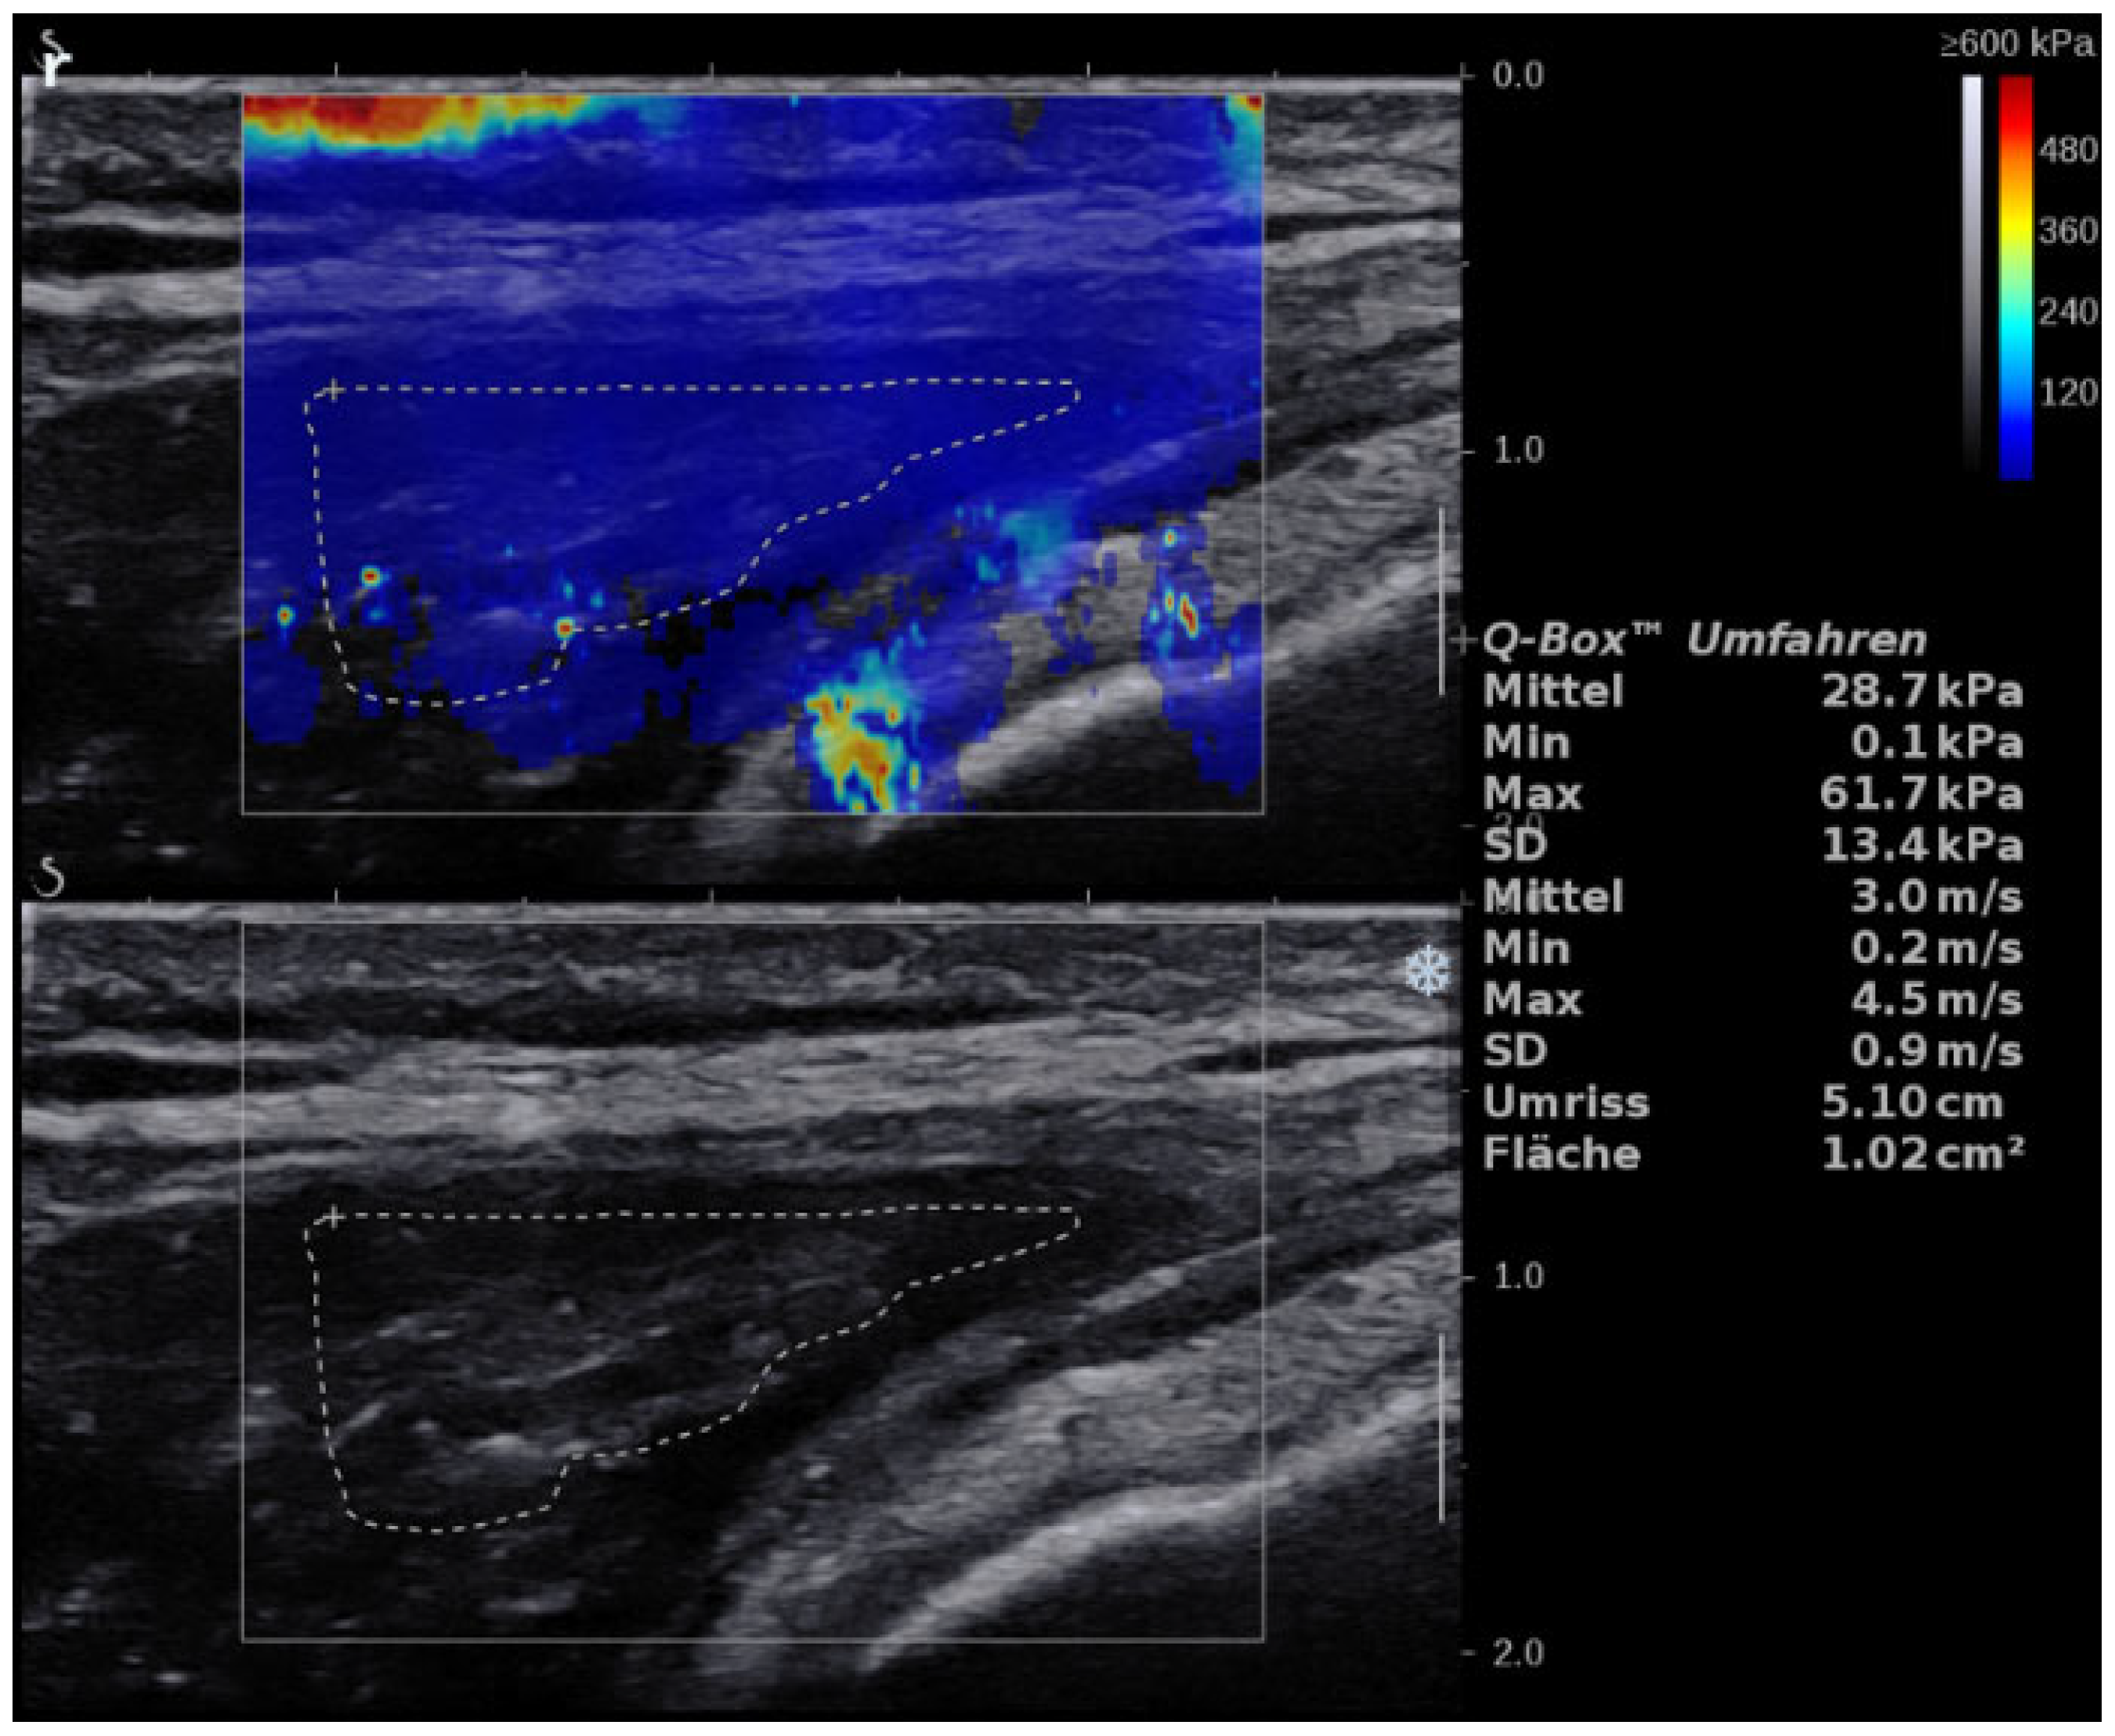

2.2. US Examination

3.3. GM